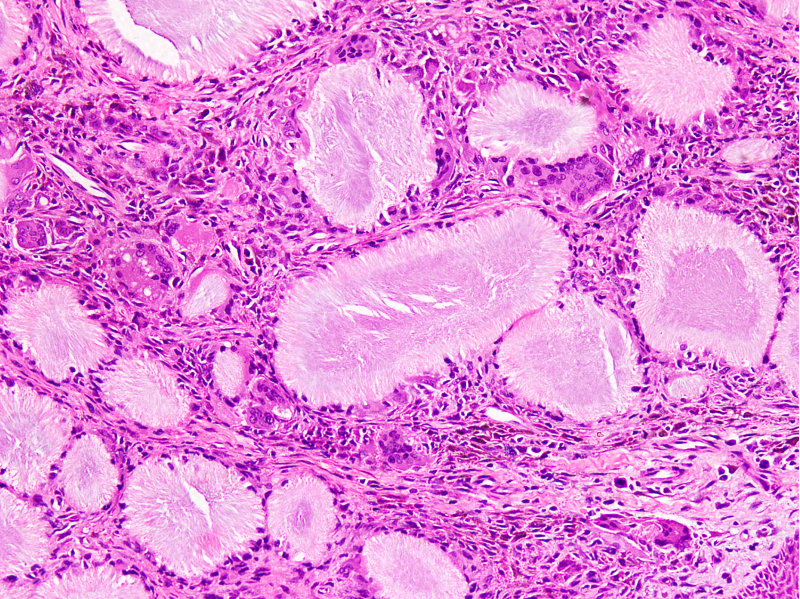

Microscopic (histologic) description

- Gout tophus:

- Nodular aggregates / granuloma-like appearance consisting of acellular, amorphous, pale eosinophilic material surrounded by palisading arrangement of histiocytes and multinucleated giant cells (Dermatol Online J 2015;21:13030)

- Feathery appearance in some deposits due to empty needle shaped spaces (Skeletal Radiol 2020;49:1325)

- Presence of monosodium urate crystals (MSU) is diagnostic

- Needle-like crystals that measure 5 - 25 micrometers in length

- Brightly anisotropic under polarized light

Microscopic (histologic) images